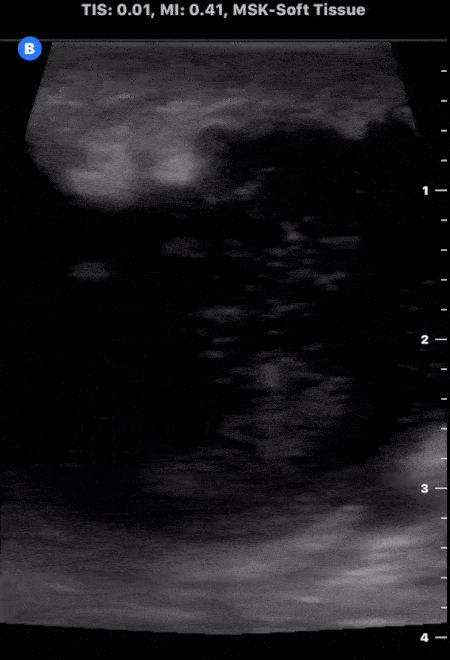

Soft Tissue - Large Soft Tissue Abscess

This is an example of a large soft tissue abscess. Note the presence of a large well circumscribed fluid collection taking up the screen. Particulate can be seen throughout the fluid collection signifying increased density from purulent material. Michael Macias, MD